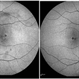

- Stargardt disease, macular dystrophy, autofluorescence imaging

AUTO FLOROSCENCE IMAGING - Description

- Fundus image and autofluorescent image of right eye of a 26-year-old male with large area of RPE atrophy over macular region surrounded by pisciform flecks. Note the flecks are better appreciated on autofluorescence images (classic hypofluorescent pisciform lesions).